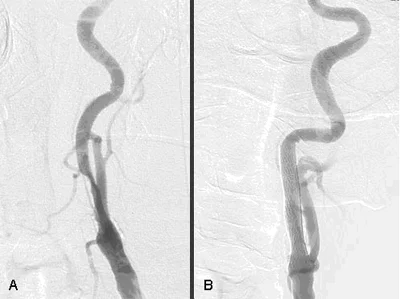

Angiogram:

An angiogram is a picture of the arteries. This picture is taken after a physician, using wires and tubes (called catheters), enters into the artery and injects a speical dye into the bloodstream. This dye helps capture photographic images, under ultraviolet light, of the arteries and other blood vessels. An advantage of this procedure is that it can help identify exactly where the diseased segment is.

Angiogram Cath Image